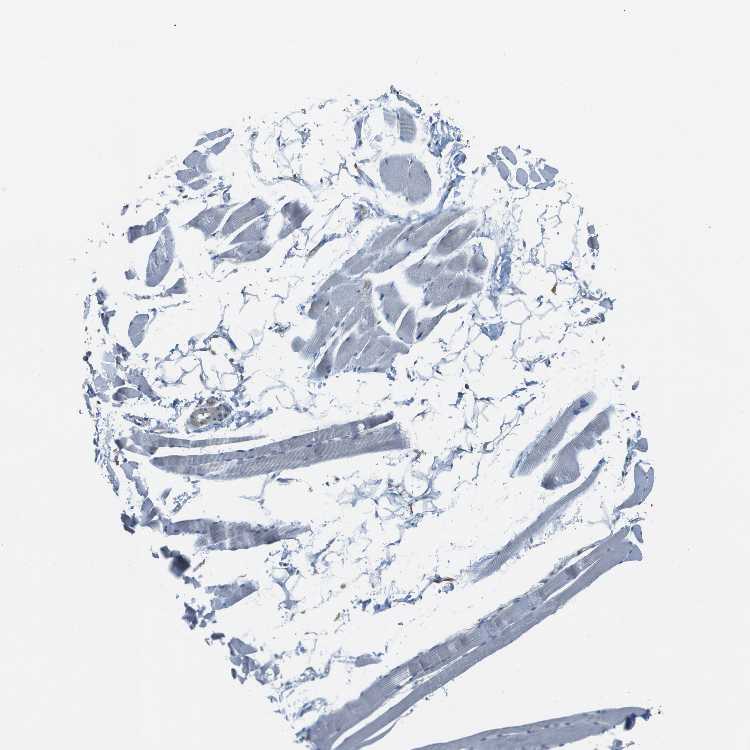

TISSUE PRIMARY DATA SKELETAL MUSCLE Show tissue menu

SKELETAL MUSCLE - Antibody stainingi

Antibody staining in the annotated cell types in the current human tissue is reported as not detected, low, medium, or high, based on conventional immunohistochemistry profiling in selected tissues. This score is based on the combination of the staining intensity and fraction of stained cells.

Each image is clickable and will lead to virtual microscopy that enables deeper exploration of all samples and also displays staining intensity scores, fraction scores and subcellular localization as well as patient and tissue information for each sample.

Antibody HPA070456Antibody CAB017616

Myocytes Not detectedNot detected